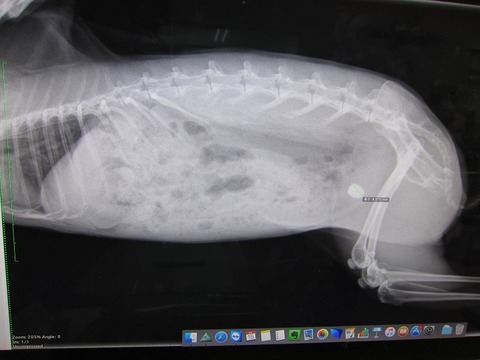

まさかあの9mmの石が出るとは…何で出たんかとかお話の前に、

まずは、石ゼロを確定させるべく早々レントゲンへ。

8.9てぇ!めちゃデカなってるし!

すんごい早くない?あまりにデカなるの早すぎひん

そして、膀胱内には溜まる砂はほとんど確認されない…。

膀胱に入り次第すぐ固まるんかいな

一番最初の手術で摘出した結石よりほんの少し小さいくらいでほぼ同じ大きさ。